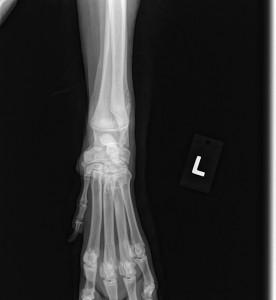

2) He is collapsed in the pasterns and flat footed, bad hips, eastie westie, swollen legs/feet

The Vet watched him gait prior to sedation and his hips and gait is really wonky. It is too early to do proper x-rays on his hind end to determine a lot but, under sedation, his Vet got a great look at manipulating his hips and joints and no crepitus noted at this time.

With his collapsed pasterns, flat feet etc. the Ester C should help greatly. With good nutrition, proper vet care and exercise, we should see marked improvement yet, he is a victim to bad genetics(breeding), and sadly, neglected/abused.